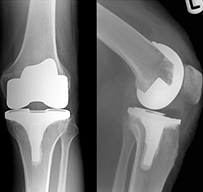

There are two main types of surgery, depending on the condition of the knee: total knee replacement and partial (half) knee replacement. A total knee replacement involves removing the damaged articular cartilage surfaces at the end of the thigh bone and the top of the tibia (the knee joint), and replacing them with a prosthetic (man-made) joint.